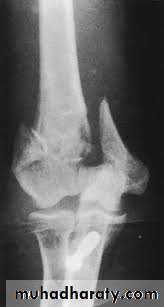

Radiology

Type A: an extra-articular supracondylar #.Type B: An intra articular unicondylar #.

Type C: Bicondylar # with varying degree of comminution.